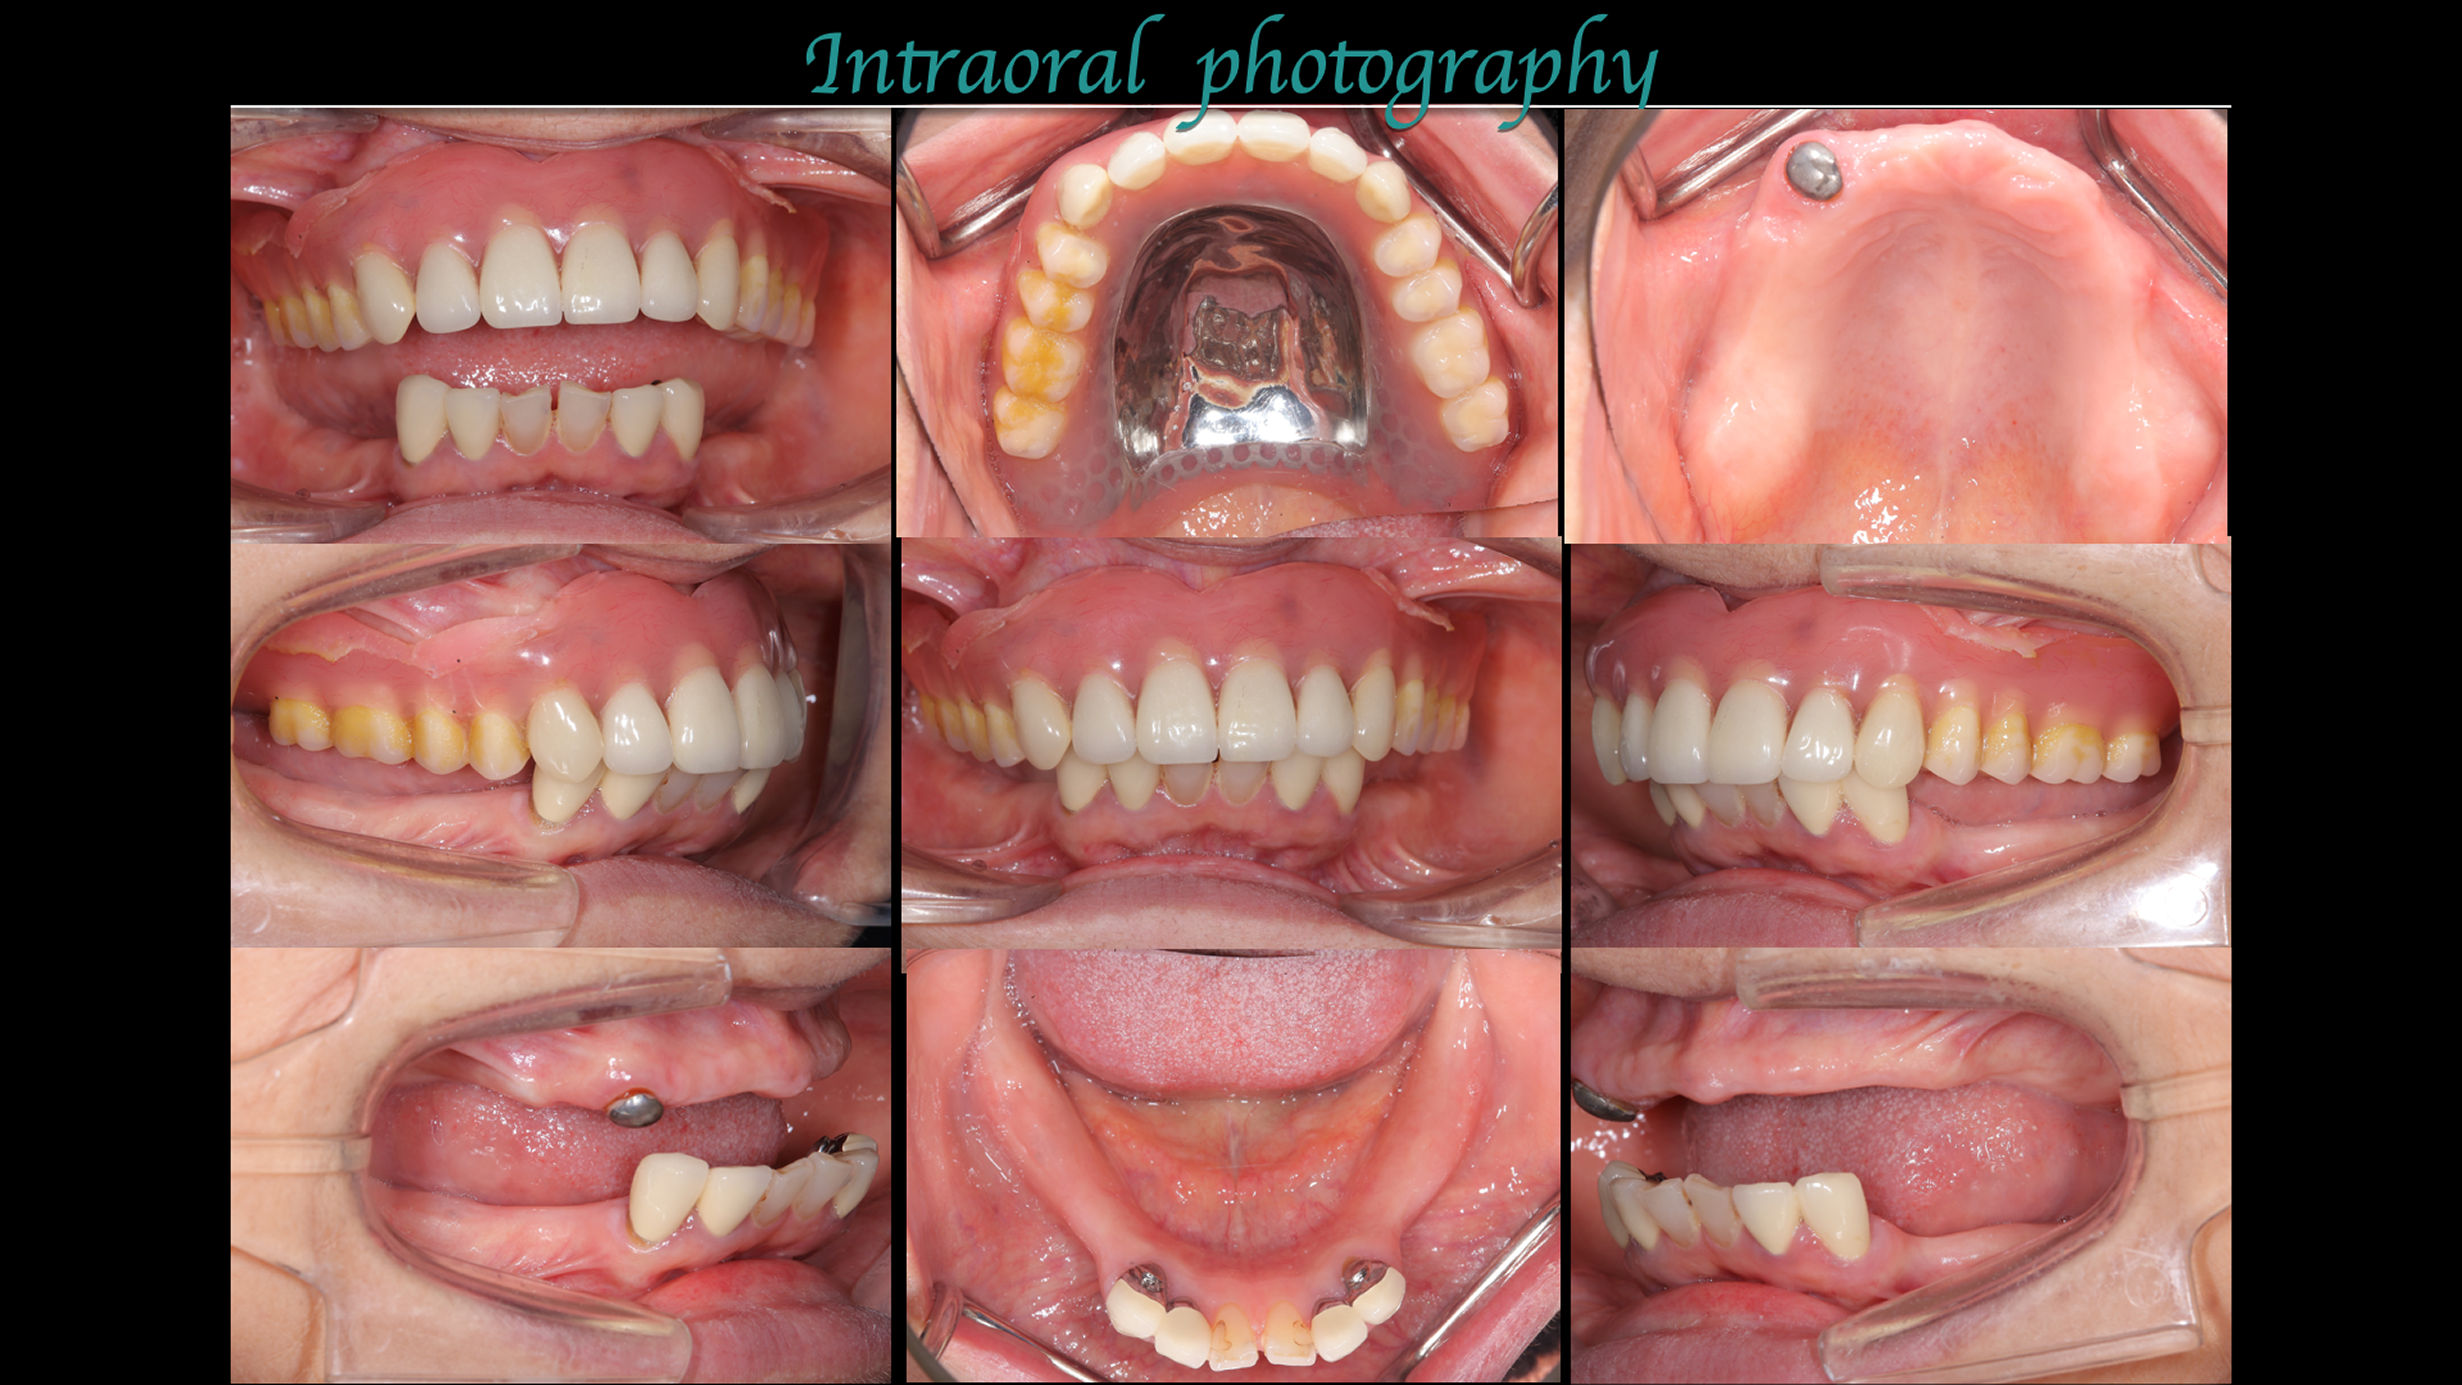

主訴:左下の歯が外れた。

治療概要:左下の歯が外れたことがきっかけで来院されました。右下と左上には歯がない状態でした。

治療前

治療後

生理的咬合と判断に至った背景

外れた左下の歯ですが、歯茎から出ている歯の部分が明らかに短く、この状態で被せ直しをしても維持力がないためすぐに外れてしまう事が予想されました。

また、奥歯がないためこの歯には噛む時の力が過剰にかかってしまいます。

この方の場合右の歯も少なく、主訴である左下の歯だけ治療をしたとしても今残っている歯も含めてどんどん悪くなることが予想されました。

このような理由で口腔全体を含めた「全顎の治療」計画を提案させていただきました。

現状残っている歯の状態から、この患者さまは「生理的咬合」であると診断し、現状噛んでいる歯の位置の修正とは行わずに、歯がないところ、歯が欠けているところを治すだけで安定すると考え治療を行っています。

行った治療

この歯(黄色の印)は顎を横に動かした時に強い力が加わり、歯の周囲の組織にダメージが出ているため、力をコントロールするために歯の形を修正が必要です。

右の奥歯についても歯が伸びてしまっているのでこちらは部分的な矯正治療と歯茎の手術で対応しています。

期間:2年

費用:280万円

デジタルシミュレーションを駆使したことで、術前の「生理的咬合である」という診断に基づいた精密な治療計画の立案が可能となりました。

治療期間はかかりましたが、計画通りに全顎の機能回復を達成し、「安心して噛める」状態を取り戻すことができました。

治療は完了しましたが、この状態を長く維持するため、今後はメンテナンスでの噛み合わせのチェックが非常に重要となります。